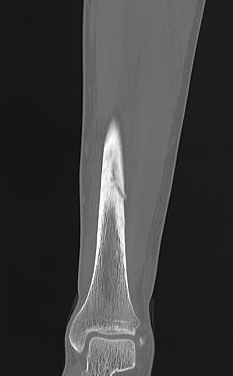

Xray

Cortical thickening

Look for "dreaded black line" - sign of fracture

Periosteal thickening with possible "dreaded black line"

Anterior cortical thickening with dreaded black line

CT